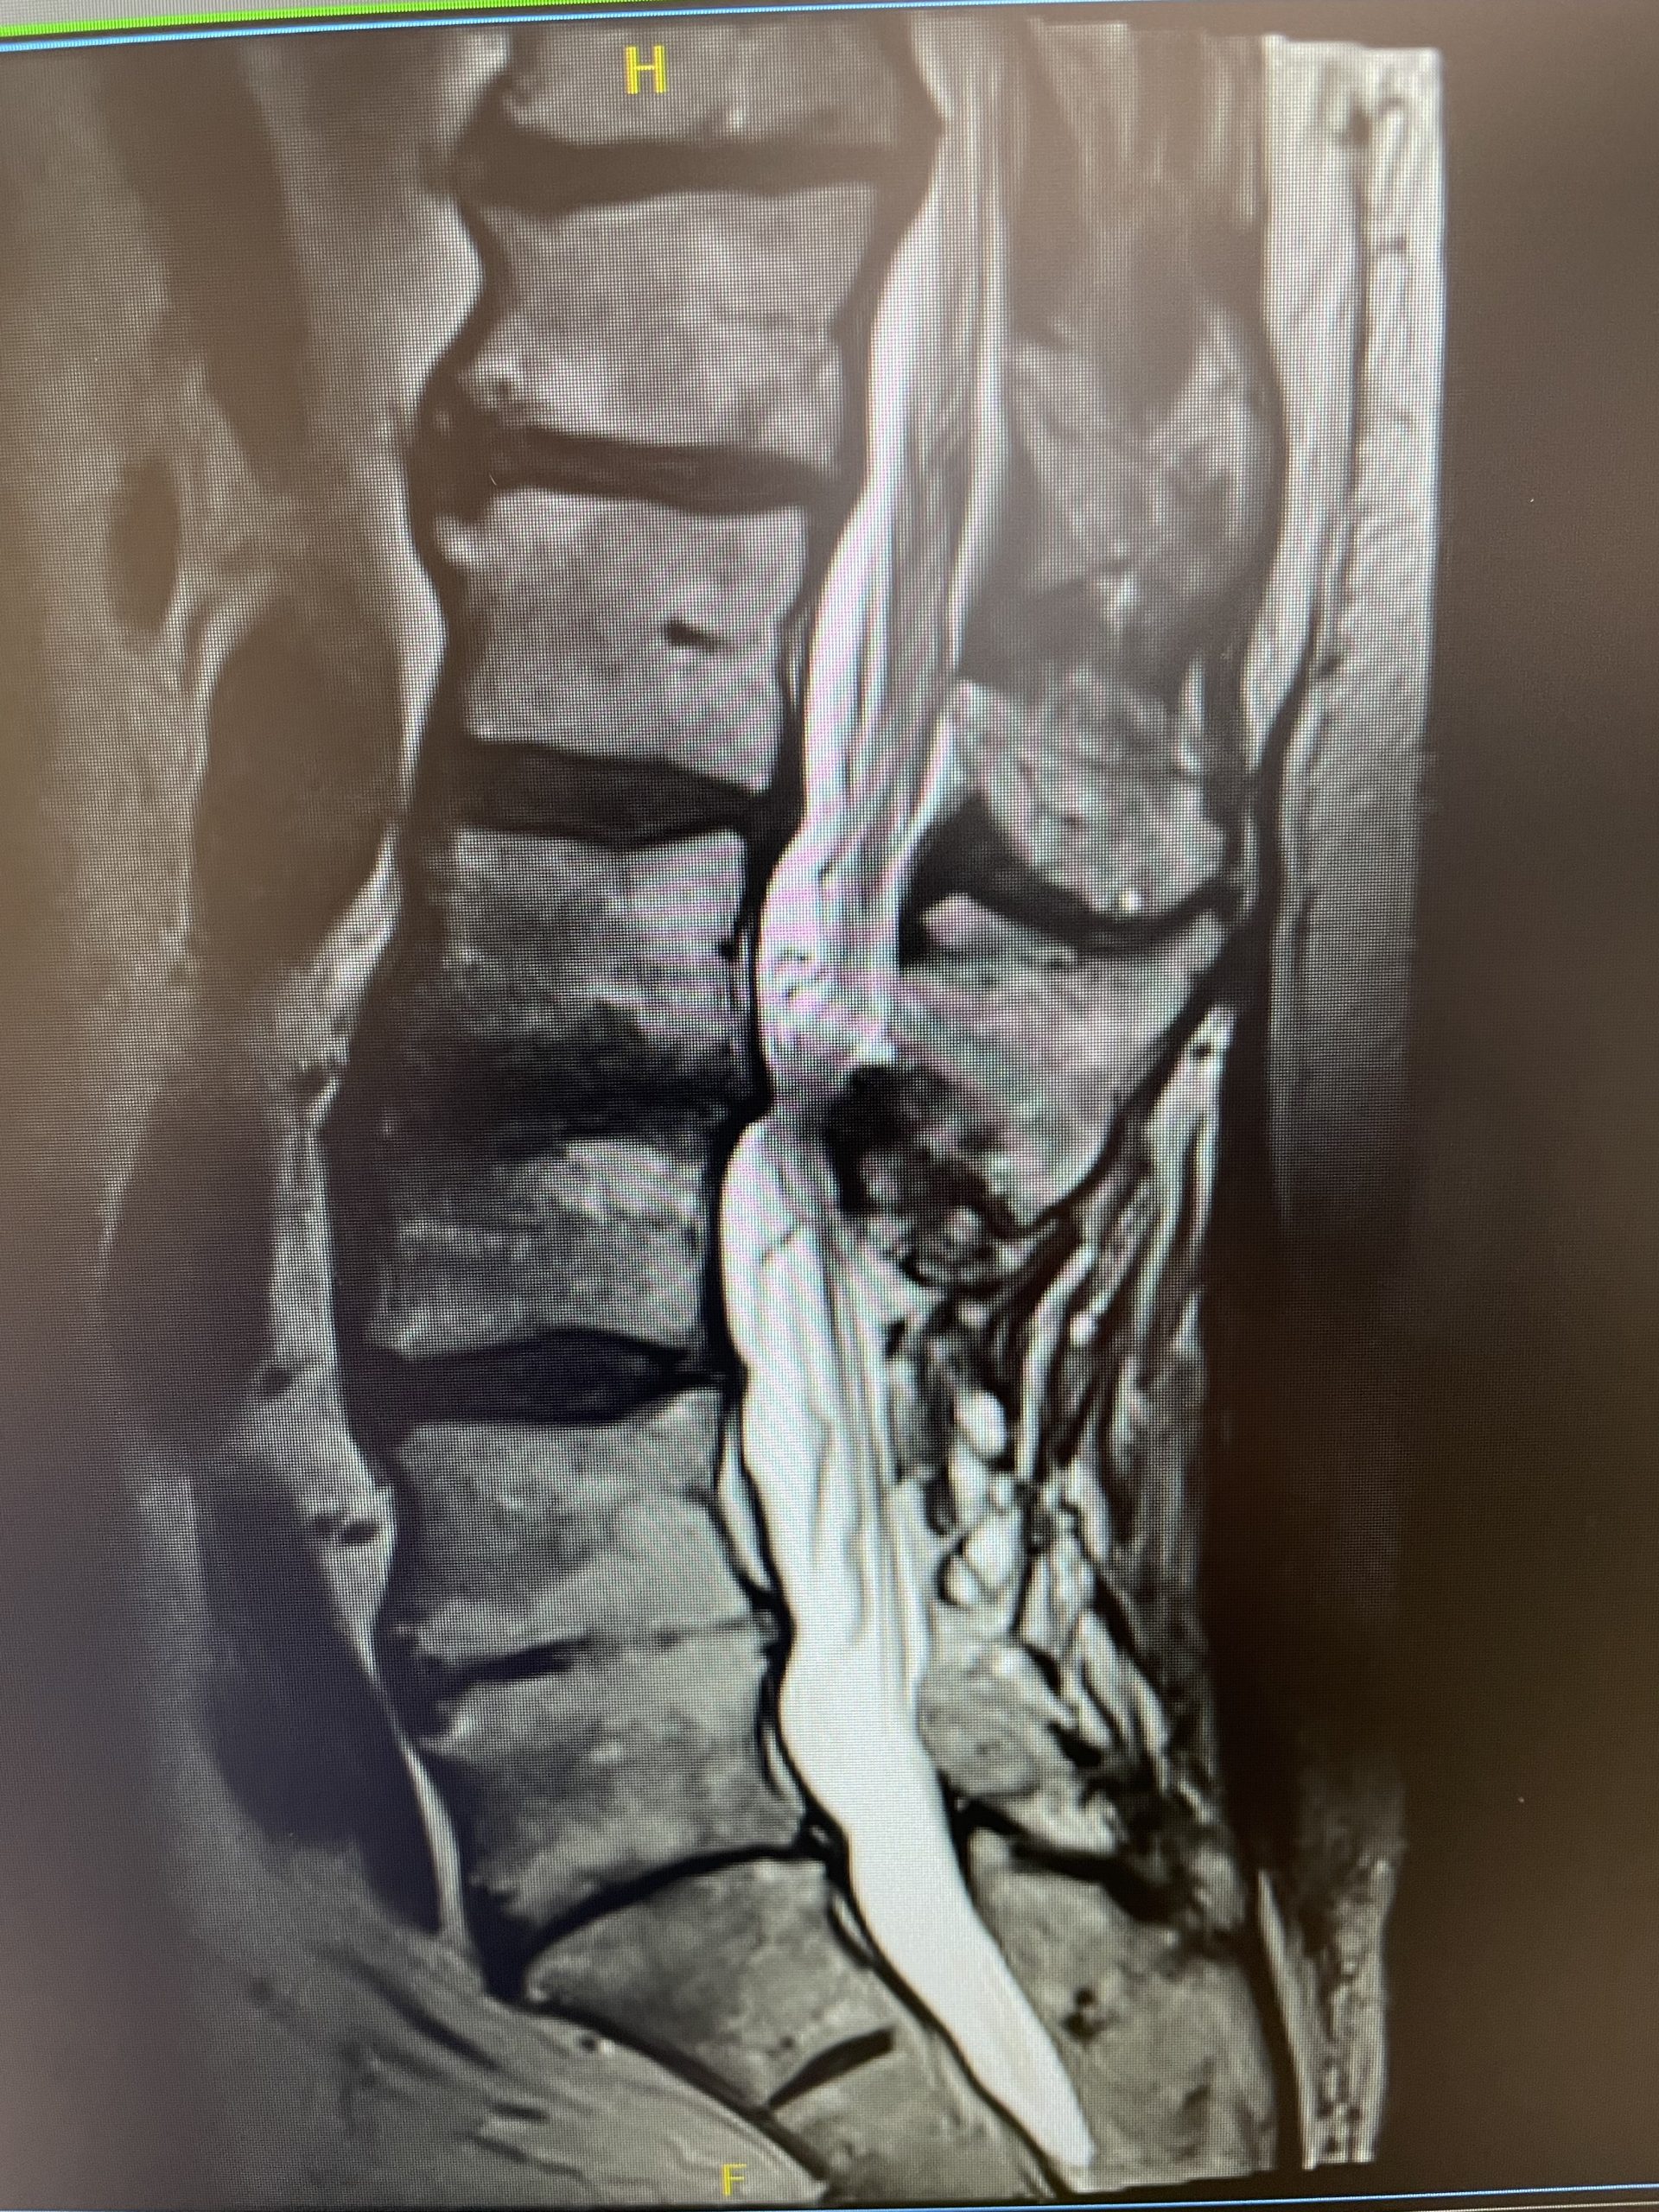

A 35-year-old female presents with severe low back pain and progressive left leg pain. She had initially presented nine months prior with mainly low back pain with mild left leg symptoms. She had an MRI (Fig 1) demonstrating a transitional L5 lumbar vertebra. This L5 vertebra is sacralized in that it is more anatomically associated with the sacral level with a rudimentary disc between it and the segment below. Because of the rudimentary disc there is very little movement at that level, hence more stress is put on the segment above.

Figure 1